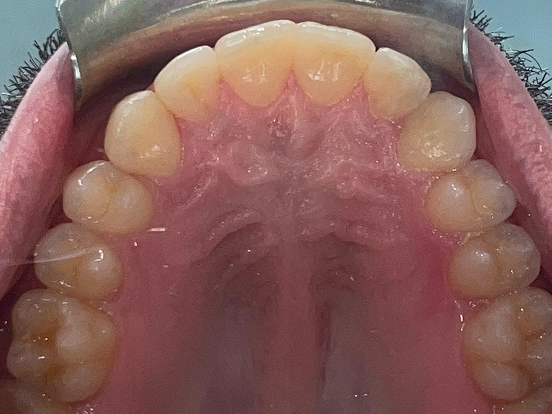

Invisalign DT

DT’s transformation with Invisalign is a perfect example of how advanced orthodontic technology can deliver incredible results. The clear aligners gradually corrected the alignment and bite issues, creating a straighter, healthier, and more attractive smile—all without noticeable brackets or wires.